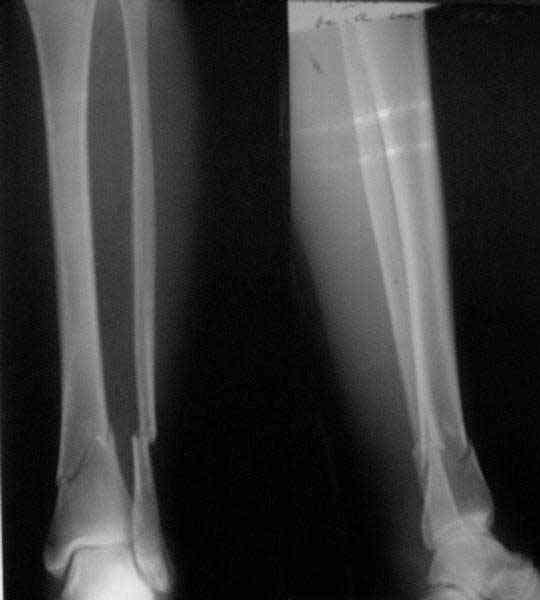

A typical case is attached, also an image with intra-op reduction obtained by a small wire distractor, in the moment of insertion a Poller wire in AP direction. Fixation by a SIGN nail. Despite the fibula was not fixed healing was obtained with the unchanged alignment.

[ Ответить ]